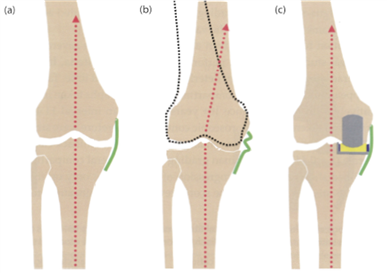

什么是UKA?

单髁置换术属于保膝手术的一种,它是对内侧间室的病变进行重新研磨修补,恢复内侧副韧带的张力,将下肢力线恢复到没有发生膝关节OA之前的状态,与全膝关节置换不同的是,它没有干扰膝关节周围的韧带排列,保留了我们的外侧间室、外侧半月板、前后交叉韧带和髌股间室,手术创伤小,符合自然膝关节的活动轴线,最大程度的保留了膝关节周围的本体感觉,即使接受手术的内侧间室,也最大程度的保留了骨量。

UKA纠正膝关节力线示意图。